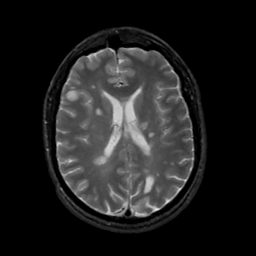

MR Study #2, February 17, 1991 -- Slice #30

[Home][Help][Clinical][Tour 1][Tour 2] Slice 30